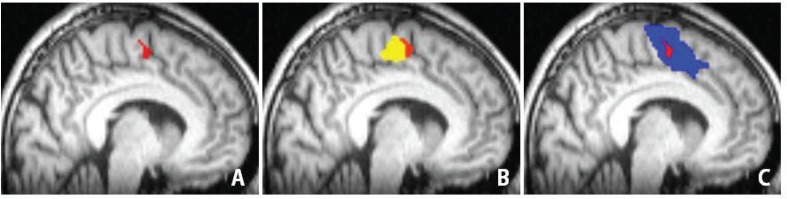

Fig. 5A demonstrates an overlap region of motor and language-SMA. According to the MNI template, 0 of the x-axis and y-axis indicate the midpoint of the anterior commissure. The SMA proper and pre-SMA are assigned by positive and negative value of y-axis, respectively. The MNI coordination of the overlap region were (−8/−10/59) of x/y/z, which indicated it is located posterior to the anterior commissure in the left hemisphere. Therefore, the overlap region is involved by the SMA proper. The region was 0.19 cm3 of volume, which should be an intensive center of SMA (Fig. 5A). We termed this center the SMA core. Language-SMA included additional areas anterior to the SMA core, whereas the motor tasks evoked activation in regions posterior to the SMA core (Fig. 5B, C).

Fig. 5.

Spatial relationships among the supplementary motor area (SMA) core and other SMA activity. Areas shaded in red (A) represent the SMA core, which was located in the x/y/z positions of −8/−10/59 on the Montreal Neurological Institute (MNI) template. Areas shaded in yellow (B) and blue (C) represent the activated areas during right finger tapping (rFT-SMA) and lexical decision task (LDT-SMA), respectively. The red SMA core was involved by rFT-SMA and LDT-SMA.

Our fMRI study demonstrated sets of two representative activation patterns, such as LDT- and rFT-SMA, and verified anterior dominance of language functions. Although we found a similar rostro-caudal gradient, stimulation and resection of the overlapping area consistently caused severe language and motor deficits. According to previous and our studies, at least in part, we believe that the overlapping area plays a major role in all behavior executions.20) Our normal volunteer study delineated possible existence of the SMA core (Fig. 5). In addition, resection of posterior part of LDT-SMA including the SMA core caused severe, but transient neurological deficits. Although the SMA core is plausible in the posterior part of SMA, it is still necessary to precede further basic and clinical research about anatomy and functions of SMA.